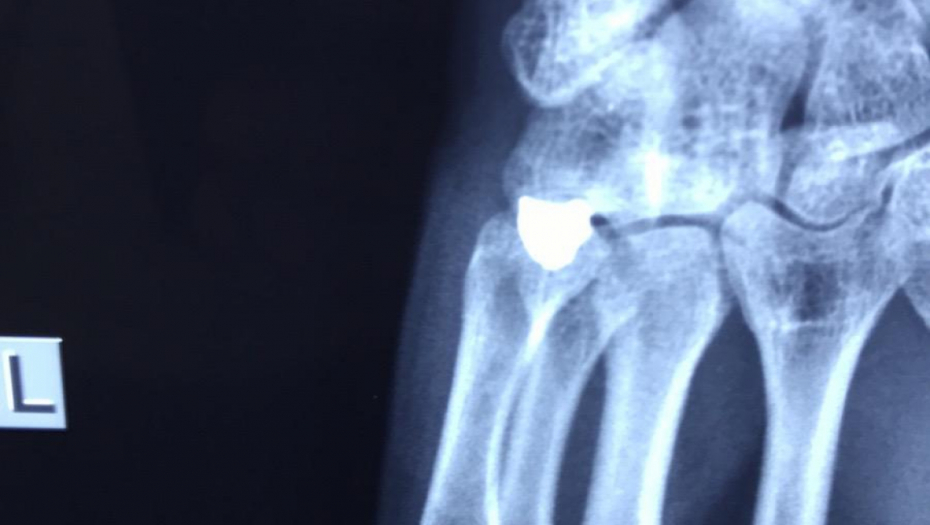

OBJAVLJEN RENDGENSKI SNIMAK Ovo je metak koji je izvađen iz šake srpskog mladića (FOTO)

U KBC Gračanica Miloš S. (21) izvađen metak koji je bio u šaci.

Ovde možete pogledati i rendgenske sinimke šake ranjenog mladića.